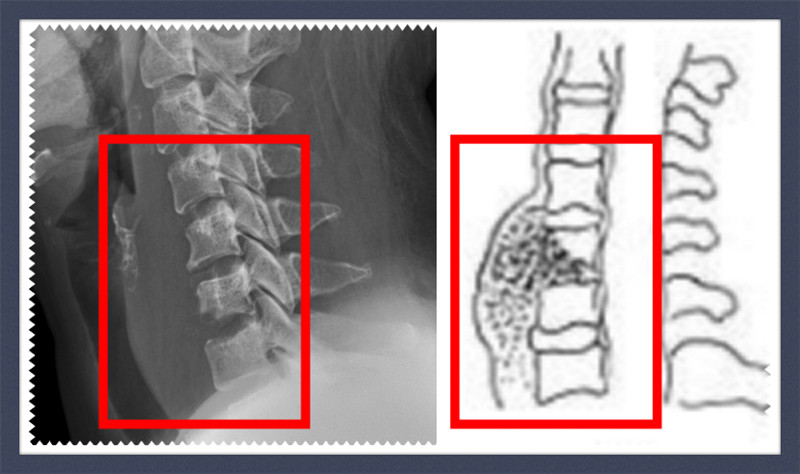

40岁的谢女士,一月前出现颈部疼痛、咽部不适以及肩部不适,在外院考虑为“咽喉炎”,予以咽喉炎相关治疗后颈部疼痛无明显好转,伴左肩部酸胀不适,左前臂内侧麻木。谢女士的症状无好转反而出现逐渐加重的趋势,来到我院骨科高级专家吴富华主任门诊就诊,吴主任考虑谢女士可能得了“颈椎结核”,住院治疗。谢女士住院后,高增鑫副院长带领骨科团队针对谢女士的颈部疼痛、咽部不适并伴右肩部不适的症状,结合影像学检查后诊断为“1、颈6椎体结核;2、食管后壁脓肿”。

结核杆菌进入血液循环系统后,在颈椎附近“安家落户”,产生脓液、形成病灶,谢女士其中有一处颈椎的右侧骨质部分已经被结核杆菌吞噬得“面目全非”。由于颈椎位置距离人的呼吸、心跳中枢都较为接近,颈椎结核若不能得到及时有效的诊治,结核杆菌会逐步对颈椎“吞噬”,其产生的脓汁、肉芽、干酪样物质、死骨和坏死椎间盘等可凸入椎管内,压迫神经根和脊髓,病变椎体的脱位或半脱位亦可使脊髓受压,患者可出现痉挛性瘫痪。谢女士如果再晚一段时间,很有可能因脊髓压迫而导致高位截瘫,所造成的病残十分严重,故对本病应早期诊断、治疗及预防。